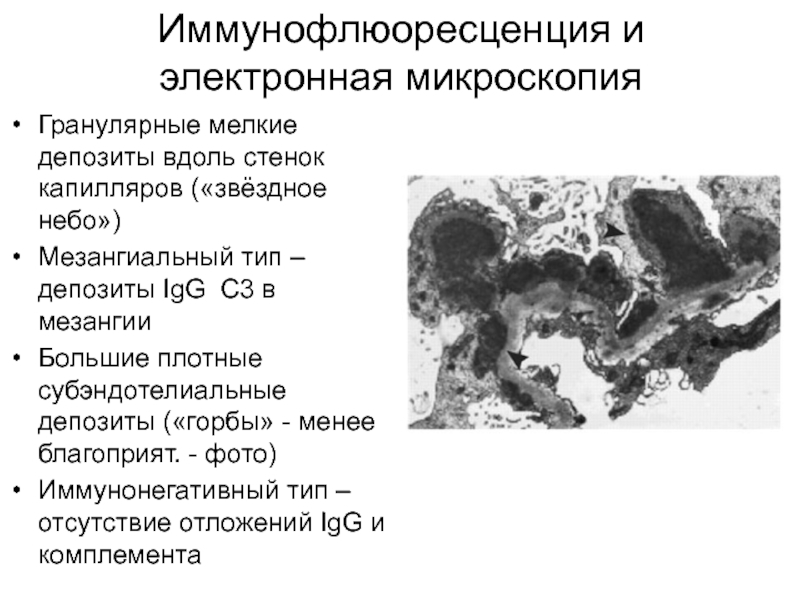

Механизм остро го диффузного гломерулонефрита